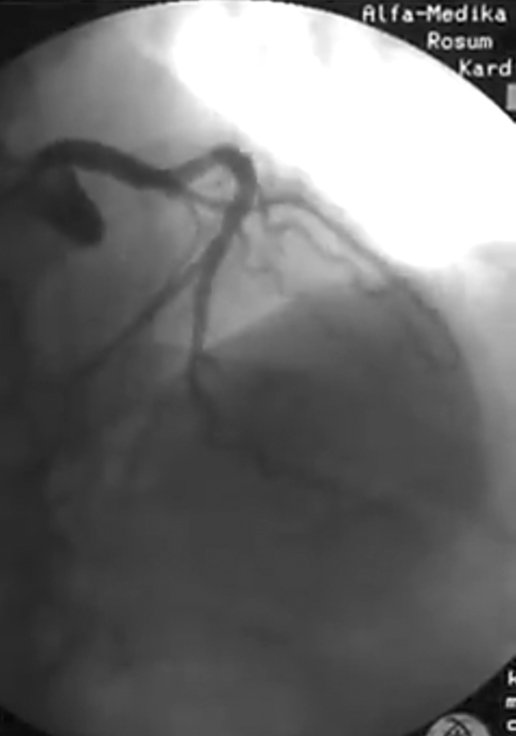

В Кременчуге заработала программа «Стоп-инфаркт». В этом году на нее выделено 2 миллиона гривень – средства направят на проведение ургентных стентирований при остром инфаркте миокарда. По информации главврача Объединенной больницы «Кременчугская» Виктора Сычёва, финансирования хватит на выполнение 100 коронарографий (обследование артерий, при котором выявляются места их сужения) и 75 стентирований.

Кто может получить бесплатное лечение? Как отмечает врач, стентирование сердца проводят в остром периоде инфаркта миокарда, которому не более суток. Поэтому, если сердце «давит» с понедельника, не стоит затягивать с вызовом «скорой помощи»: при своевременном обращении у вас есть шанс попасть под действие программы и получить дорогостоящее лечение (стоимость процедур около 20 тыс грн) за бюджетные средства:

Кроме бесплатной коронарографии и установки стентов программа предусматривает обеспечение таких пациентов бесплатными лекарствами в течение первых суток лечения. Для этого из бюджета выделены 350 тыс грн.